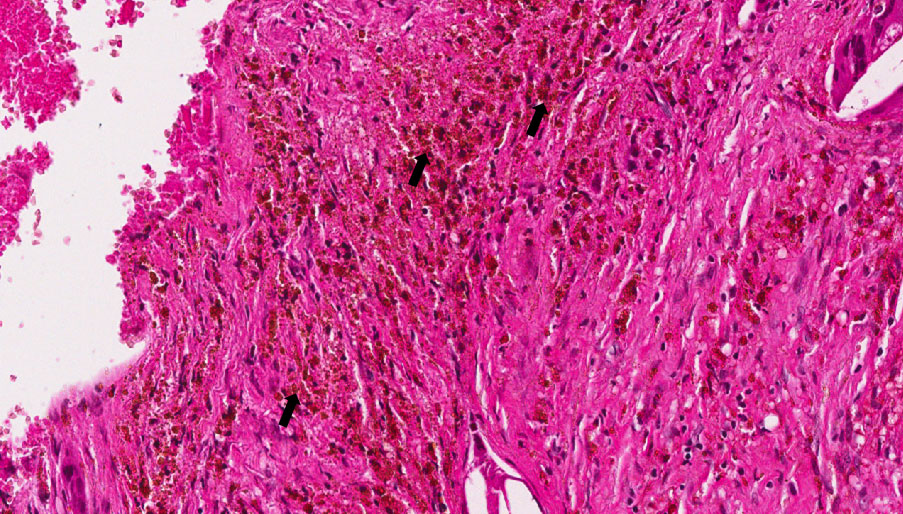

É um pigmento resultante da destruição da hemoglobina (pigmento que confere a cor vermelha às hemácias), sendo consequência do depósito em excesso de ferro.

Fragmento de mucosa bucal no tecido conjuntivo podemos observar inúmeros cristais de colesterol, alguns com células gigantes justapostas. Em áreas focais, nota-se degeneração hialina do conjuntivo caracterizada por focos de aspecto róseo, homogêneo e vítreo. Focos de hemorragia e hemossiderina (setas) também podem ser notados.

Observar hemácias aglomeradas no tecido conjuntivo e pigmento de coloração acastanhada e birrifringentes.

Granuloma Periapical